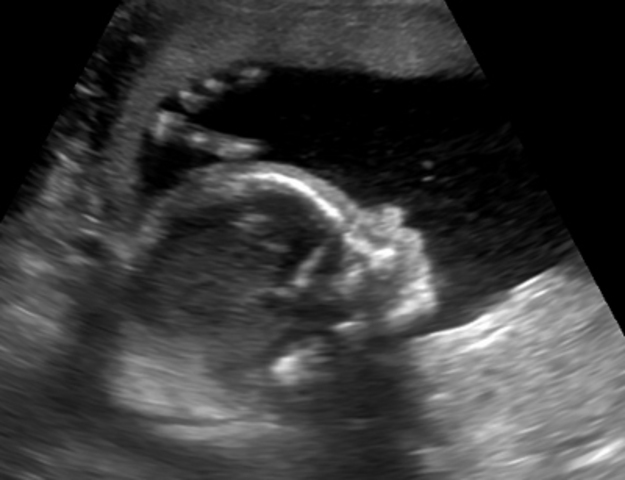

• Month 3

Month 3

In month 3, the digestive system starts functioning. Movement of the limbs are prominent by the end of this month.